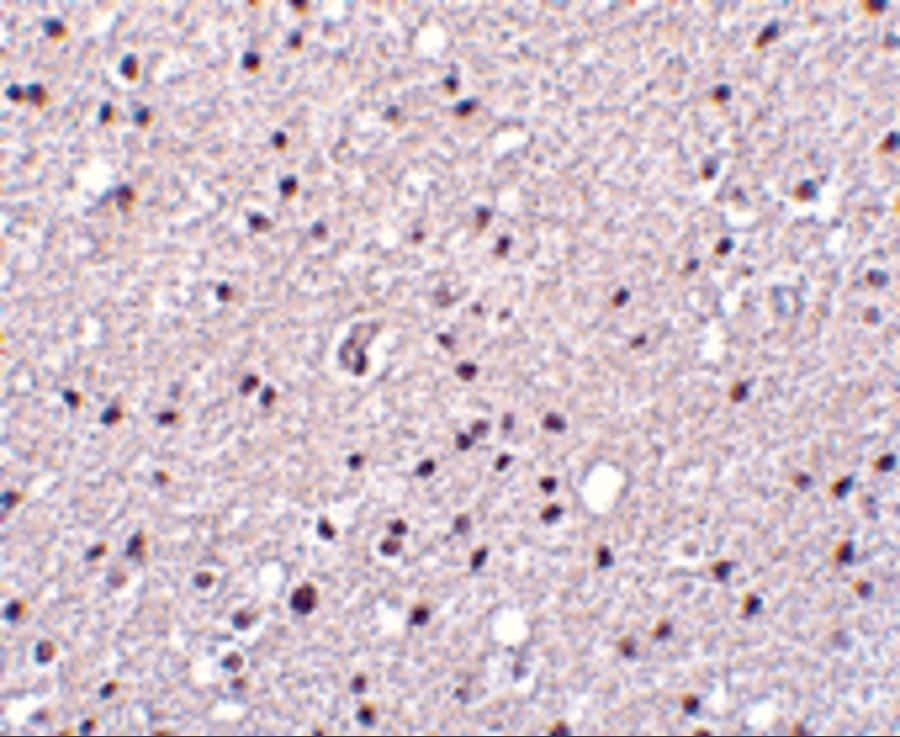

Supportive validation

- Submitted by

- Invitrogen Antibodies (provider)

- Main image

- Experimental details

- Immunohistochemistry of Neurotrypsin in human brain tissue with Neurotrypsin Polyclonal Antibody (Product # PA5-20363) at 2.5 µg/mL.